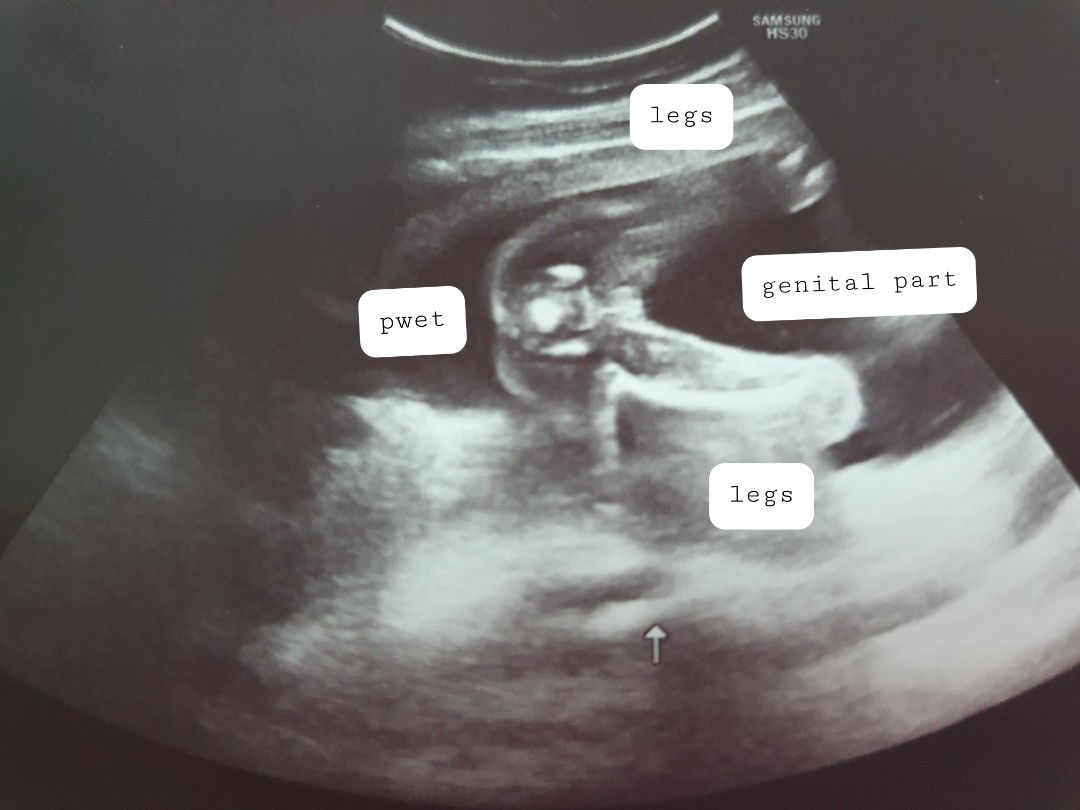

Baby Girl?

sure po na baby girl?

pano po masasabi/malalaman na 100%?